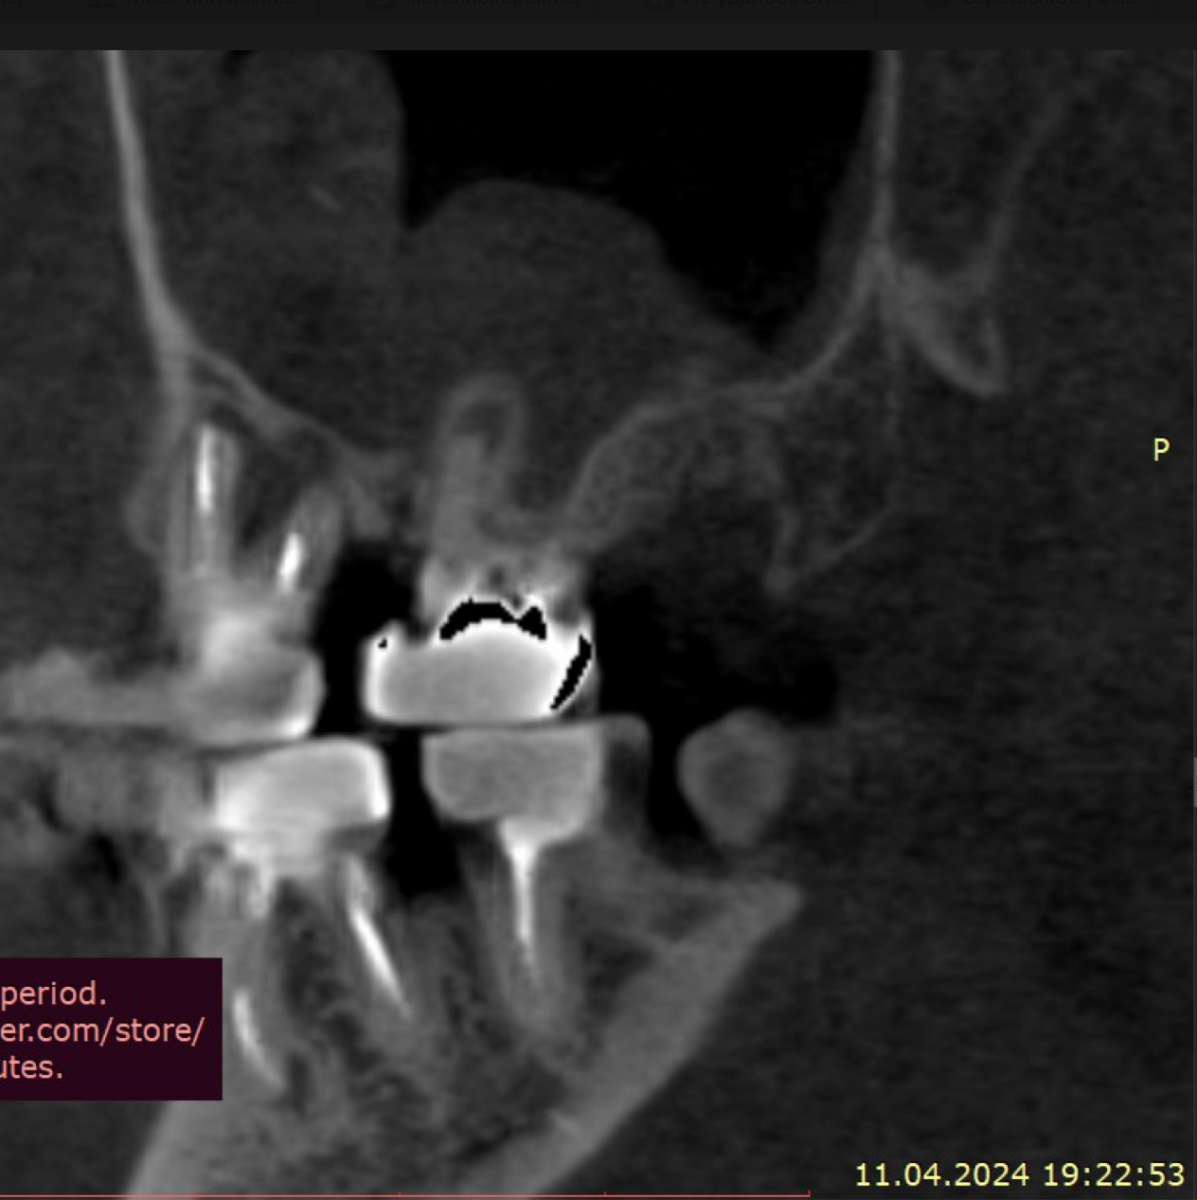

Sergey32132 Опубликовано 5 декабря, 2025 Поделиться Опубликовано 5 декабря, 2025 (изменено) Добрый день. Зубы проблемные с детства очень сильно Полтора-два года назад предварительно удалось спасти не спасаемое, 26 и 27, по крайней мере по нескольких кт перидически, неплохой регресс и заживление костной ткани, даже в области 26 где было большое поражение фуркации, сейчас намного меньше, они не болят уже почти год, до этого очень долго болели даже после качественного лечения и врачи прогнозов не давали конечно же между 24-26 (25 нет уже лет 10) стоит адегизивный бабочка, уже не в самом лучшем состоянии, вернее зубы 24 26 не в очень хорошем, так вот я хотел снять бабочку и одеть на 24-26 металлокерамику, во рту есть несколько металлокерамик единичных, на 3 еще не ставил Есть вариант, и я послушал разных докторов, что можно было бы например 24 просто сделать реставрацию качественно, 26 там без вариантов покрыть коронкой единичной, а 25 имплантат, но я пока избегаю всего так сказать инвазивного, хотя бы еще полтора-два года, с начала 2024 и по середину 2025 болел очень тяжело, Лонг ковидом, это страшное явление которое врагу не пожелаю, возможно даже кто помнит мои темы что я у себя предполагал сепсис, вот именно у меня был он не в виде усталости какой и тд, что чаще всего, а в форме выраженного иммунодефицита + легкого но стойкого системного воспаления , по типу аутоиммунных реакций, в общем не будем вдаваться в эту тему, к тому же она не изучена еще, все только предстоит, спасибо лишь тем докторам-интузиастам, которые просто из спортивного интереса не забросили эту тему и занимаются исследованиями, при разных НИИ, в итоге они меня спасли, помогли определенные противовирусные на длительной основе поставить меня на ноги, что еще раз и том числе мой пример подтверждает вирусный генез Лонга, 1,5 жизни просто выпало у меня Ладно, я далеко ушел уже от темы, я к тому, что более современно наверное считается имплантат и 24 и 26 по отдельности, но повторюсь я боюсь пока лишних инвазивных процедур. Подскажите пожалуйста, каковы минусы моста с металлокерамики на 3 зуба, по каким причинам это считается прошлый век, и какие нюансы меня могут ждать ? Даже если те зубы я рано или поздно потеряю, но даже 3-4 года выиграть еще перед имплантацией, это все равно выигрыш Возможно я думал тот же мост на 3 но из циркония, но тоже не знаю, зубы те хоть и с положительной динамикой но сколько они еще простоят, а цирконий как никак в 2 раза дороже металлокерамики, но если лучше его, тогда рассмотрю Изменено 5 декабря, 2025 пользователем Sergey32132 Ссылка на комментарий